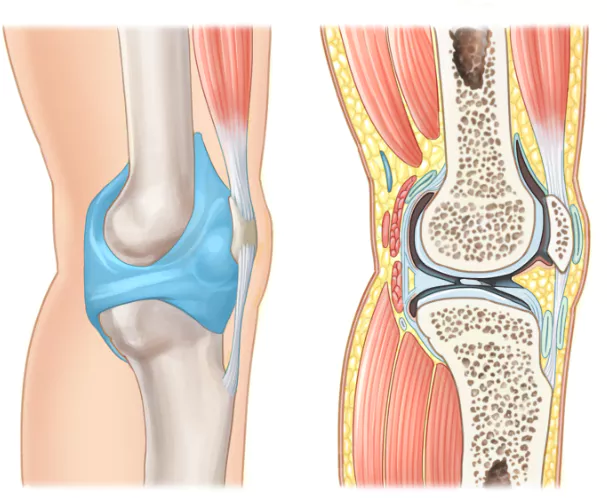

무릎 관절염은 많은 사람들에게 영향을 미치는 흔한 관절 문제 중 하나입니다. 이러한 질환이 있는 환자들은 적절한 운동을 통해 무릎 관절을 더욱 강화하고 통증을 완화하는데 도움을 줄 수 있습니다. 이 글에서는 무릎 관절염에 좋은 운동 10가지 및 주의사항에 대해서 자세히 살펴보겠습니다.

무릎 관절염은 일상생활에 불편을 초래할 수 있지만 적절한 운동과 주의 사항을 준수하면 증상을 개선하고 생활의 질을 향상할 수 있습니다.

위에서 소개한 무릎 관절에 좋은 운동은 무릎 관절을 강화하고 통증을 완화하는데 도움을 주는 것뿐만 아니라, 제대로 수행하면 다른 건강 이점도 얻을 수 있습니다.